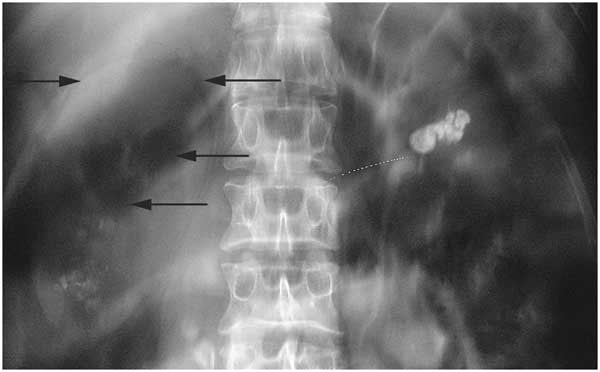

5. 신장결석

신장결석은 소변 내에 포함된 미네랄이 뭉쳐서 생기는 돌로, 오른쪽 신장에 생기면 옆구리 통증이 나타납니다.

- 통증 양상: 옆구리에서 시작해 허리, 아랫배, 사타구니까지 이어지는 극심한 통증(산통).

- 특징: 자세를 바꿔도 통증이 줄지 않고, 소변을 볼 때 피가 섞이기도 합니다.

- 원인: 수분 섭취 부족, 고단백 식단, 염분 과다 섭취.

- 치료: 수분 섭취 증가, 진통제, 체외충격파쇄석술(ESWL) 또는 내시경 수술.

- 예방: 하루 2리터 이상 물 마시기, 짠 음식 줄이기.